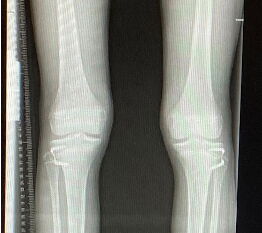

Bei offenen Wachstumsfugen kann über eine Steuerung des Wachstums mit einer Klammer (Blount-Klammer/Flex Tack) oder kleinen Plättchen (Eight Plate) eine Korrektur von Achsabweichungen in der sagittalen und coronaren Ebene erreicht werden (Abb. 8). Der Hautschnitt beträgt ca. 1,5 - 2 cm und die so versorgten Kinder können ihre Extremität direkt postoperativ schmerzadaptiert voll belasten. Die wachstumslenkende Operation mit einer Klammer oder einem Plättchen besitzt ein enormes Korrekturpotential und erspart dem Kind oder Jugendlichen umfangreiche Umstellungsosteotomien und Plattenosteosynthesen, welche eine Schnittlänge von 15 cm und eine Entlastung des operierten Beines von 4-6 Wochen erforderlich machen.

Abb. 8 a-g: Genua vara prä- und postoperativ versorgt mit Flex Tacks (a-b) und ein Genu valgum versorgt mit Eight Plate an der medialen Femurkondyle (c); Spitzfuß bei congenitalem Klumpfuß und einem Flat Top Talus mit präoperativem Röntgenbild seitlich und der deutlich nach dorsal stehender Tibia(d); intraoperative Bilder der Epiphysiodese mittels Eight Plate zur Wachstumslenkung der distalen Tibia in die Extension (e-f) und postoperativer Verlauf nach sechs Monaten mit regelrecht stehender Tibia über dem Talus durch die distale Extension (g).